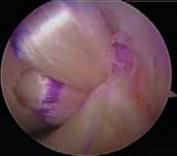

5. If the AL bundle is found to be intact, special care is taken to preserve this bundle while the overlying synovium and ruptured PCL fibers are débrided (

TECH FIG 5A

).

6. When preparing the posterior aspect of the tibia, preservation of the PCL origin is essential.

7. Tibial tunnel preparation is performed similarly to the single-bundle technique.

1. The exit point for the guide pin along the sloped face of the posterior tibial fossa is just distal and lateral to the intact PCL insertion site (

TECH FIG 5B

26. Fixation and closure are then performed. TECH FIG 5 • A. An intact AL bundle is preserved and the overlying synovium and ruptured PCL fibers are débrided. B. The exit point for the tibial tunnel along the sloped face of the posterior tibial fossa is just distal and lateral to the intact PCL insertion, as demonstrated by a long 18-gauge bent wire

A B loop.